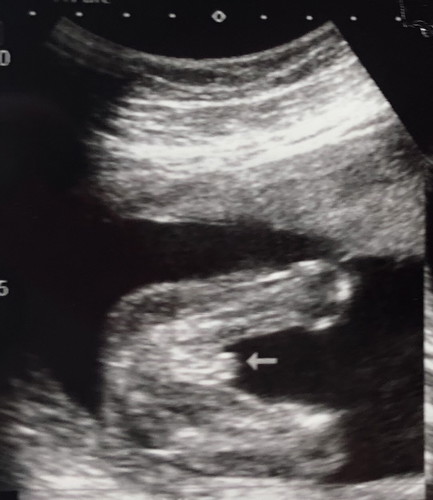

ซาวตอนอายุครรภ์ 20 wk ค่ะ ผช หรือ ผญคะ คุณหมอบอกว่า ผช 70%

อาจจะผู้ชายนะจ๊ะ ของบ้านนี้เห็นแบบนี้เลย